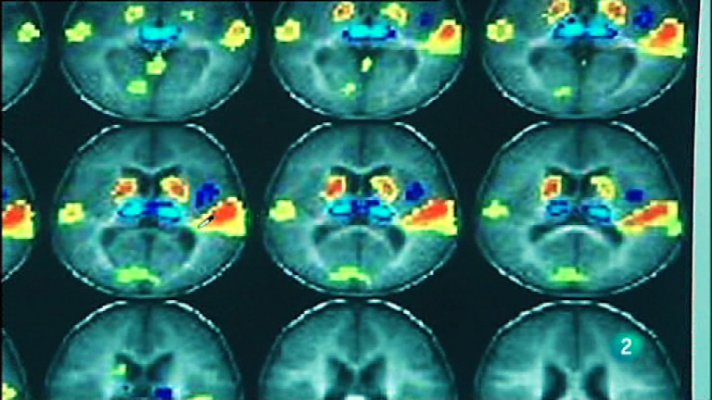

Desvelar el funcionamiento del cerebro humano puede representar el avance más revolucionario de la ciencia moderna. Viajamos hasta Alicante a conocer el Instituto de Neurociencias. Sus científicos trabajan para entender el sistema nervioso y poder curar así múltiples enfermedades